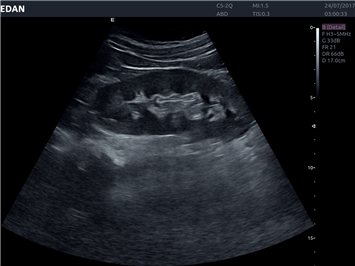

EDAN Acclarix LX4

Расширьте свои представления. Использование усовершенствованной платформой Acclarix система LX4 обеспечивает непревзойденную четкость изображений и интеллектуальный рабочий процесс для всех пользователей, являясь при этом наиболее экономичным решением.

EDAN Acclarix LX4 представляет собой инновационную ультразвуковую систему, построенную на усовершенствованной платформе Acclarix. Сочетание высокого качества визуализации с интеллектуальным рабочим процессом делает эту систему оптимальным выбором для клиник, ценящих эффективность и экономичность.

• 3D/4D-визуализация с автоматическим редактированием объема (eFace)

• Акушерства и гинекологии